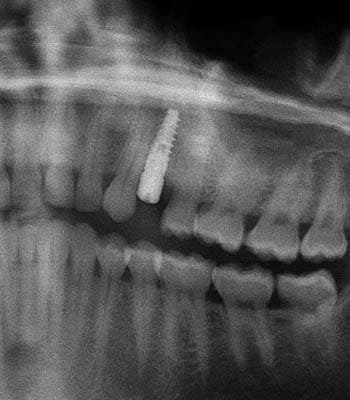

Dental implants are a titanium "root" which can be placed into the jawbone. Once integrated with your bone, the implant can be used to support a crown, a bridge, or secure a complete denture. Dental implants may be used to eliminate partial plates and dentures. The success rates for dental implants are extremely high which is due in part to the fact that root-form implants are made of a biocompatible material, titanium.